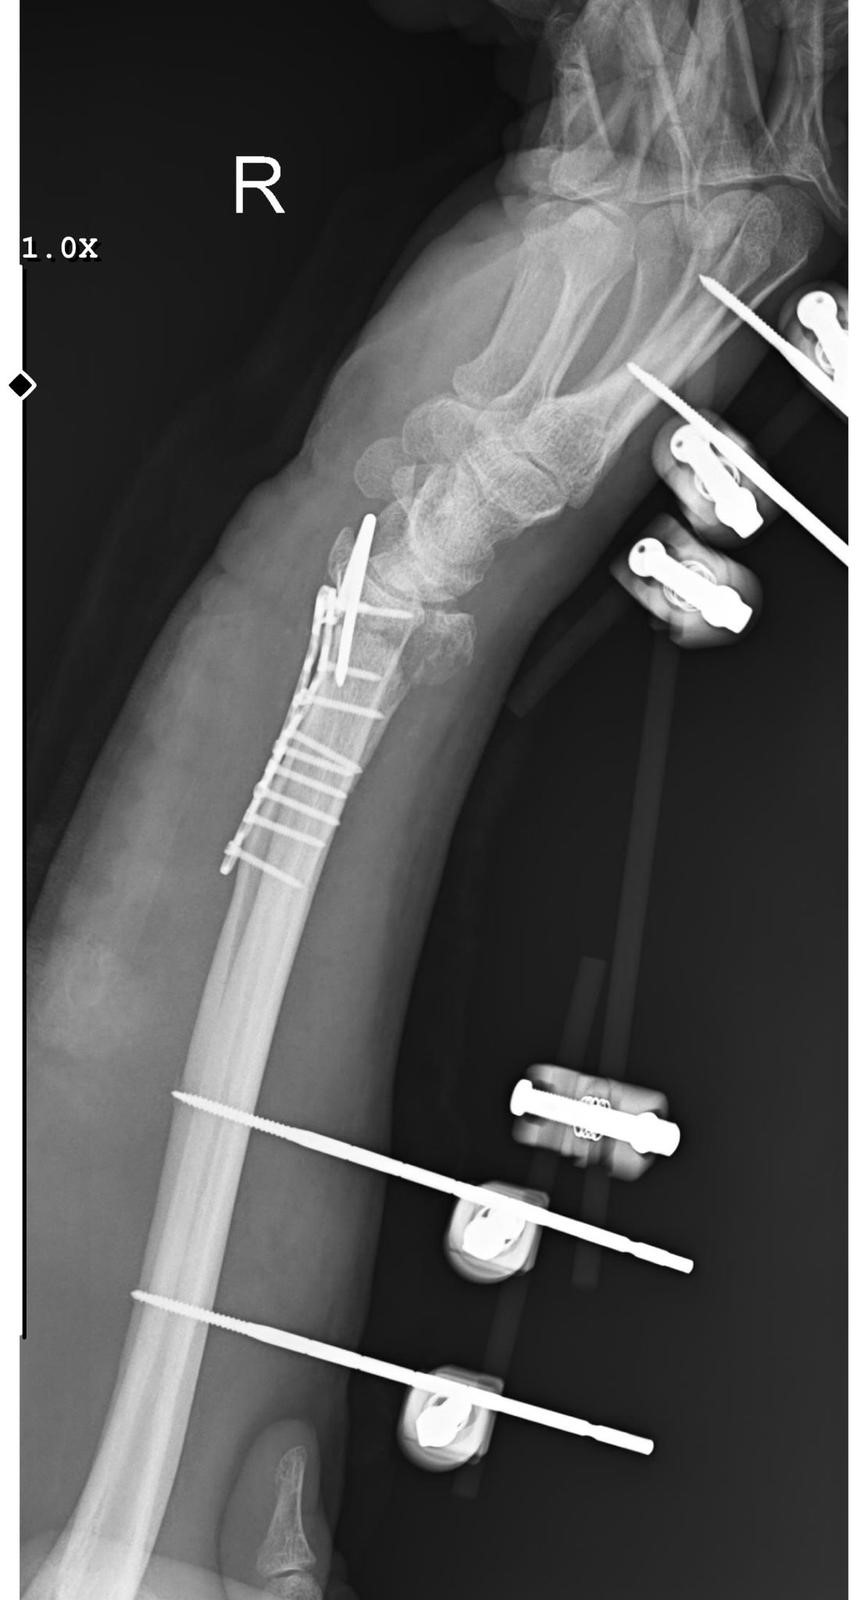

EL BİLEĞİNE 11 PLATİN TAKILDI

Hastanede yapılan müdahalede Arslantaş’ın bilek kemiğine 11 adet platin takıldığı, el bileğinde ise 15 dikiş bulunduğu öğrenildi. Yaklaşık 3 saat süren bir ameliyat geçiren Arslantaş’ın kolunda kalıcı his ve hareket kaybı meydana geldiği belirtildi. Tedavi sürecinin uzun ve zorlu olacağını ifade eden Arslantaş’ın, aylarca çalışamayacağı aktarıldı.

“Sabah apartmandan çıkış yaptığım sırada arkamdan 9 köpeğin geldiğini gördüm. Saldırgan haldelerdi ve bana saldırmak üzerelerdi. Kaçmaya çalışırken ayağım kaydı ve düştüm. Bileğimde 15 dikiş ve 11 platin var. İki ay boyunca kolum bu halde kalacak, ardından yaklaşık 2 buçuk ay da fizik tedavi göreceğim. Doktorlar his ve hareket kaybı olacağını söylediler. Bileğimden büyük kemiğin kırılması nedeniyle çok zorlu bir süreç geçiriyorum. Yaklaşık 3 saatlik bir ameliyat geçirdim.”